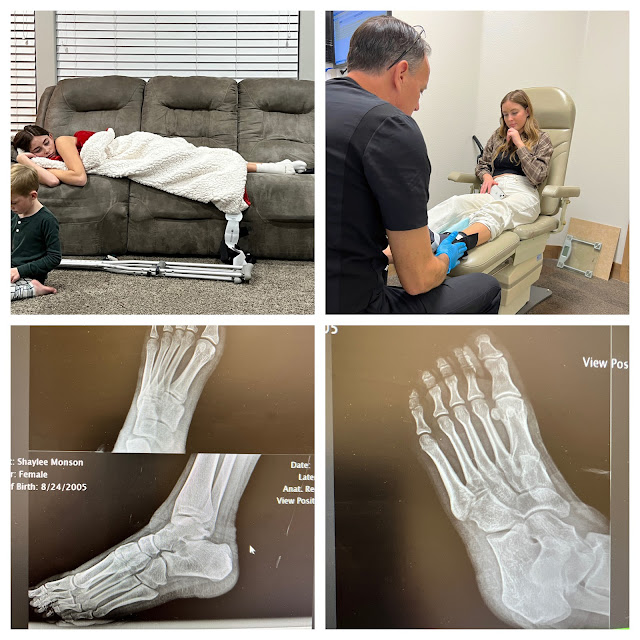

I don't think I  shared that on the first week of Open gym Shaylee sprained her Ankle really bad.  She was out for the month leading up to basketball tryouts.  On tryouts she wasn't a 100% but did what she could.  They told her she made the team, but she would have to work hard to earn her spot on the team, and get her ankle better.  Well fast forward to one game, and a tournament later and during practice she twisted her ankle again. Same one same spot.  She came home crying and on crutches.  We took her into a food and ankle specialist just to make sure everything was looking okay.  She has some nerve damage, and ligament strain but over all its not broken, but with physical therapy it will take about 4-6 weeks to play on it again.  Shaylee is super bummed, but starts therapy this week to get it stronger and better.  Here's hoping it heals fast and she can get back to playing the game she loves.